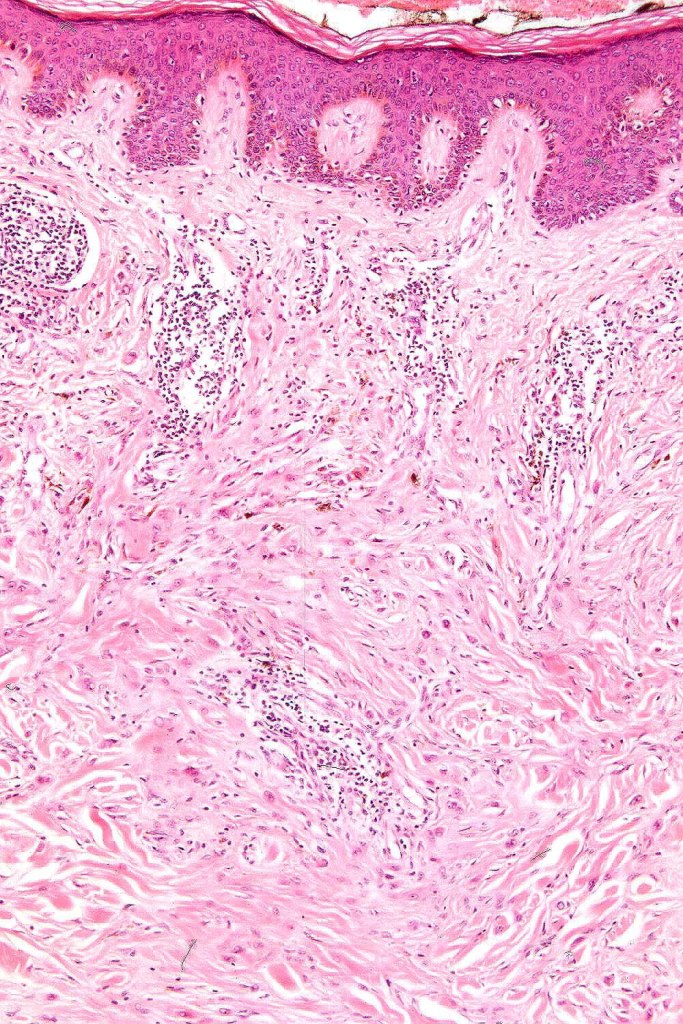

•Hyperkeratosis

•The epidermis is generally normal although sometimes acanthosis is evident

•Silhouette is either wedge-shaped or plaque-like

•Residual Spitzoid junctional nests sometimes evident

•In some cases, nested collections of spindle or epithelioid cells are present in the superficial dermis

•For the most part, the lesion is composed of somewhat pleomorphic, spindled or epithelioid cells with often abundant eosinophilic cytoplasm & vesicular nuclei with small nucleoli. Melanin is either sparse or absent

•With increasing depth (or age of the lesion), the nevus cells are separated by a dense, sclerotic stroma